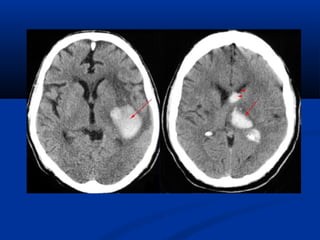

TRÒ SOÁ ÑAÄM ÑOÄ

Ñaäm ñoä cuûa nöôùc : 0 ñôn

vò Hounsfield

(HU)

Ñaäm ñoä cuûa xöông :+ 1000 HU

Ñaäm ñoä cuûa khí :–1000 HU

Ñaäm ñoä môõ :–100 HU

(ROI : Region Of Interest)

Một số mật độ (HU)Một số mật độ (HU)

Loaïi moâ Trò soå chuaån (HU) Trò soá giôùi haïn (HU)

Xöông ñaëc 250

>

Gan 65 +/– 5 45 – 75

Cô 45 +/– 5 35 – 50

Laùch 45 +/– 5 40 – 60

Haïch 45 +/– 10 25 – 55

Tuïy taïng 45 +/– 10 20 –40

Thaän 40 +/–10

Môõ - 65 +/–10   - 80 – - 100